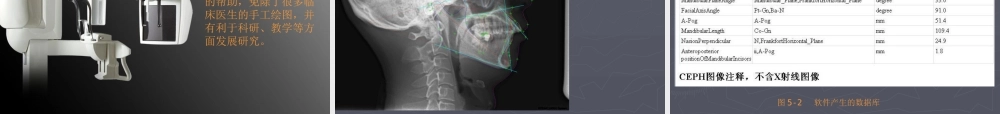

牙科三维牙科三维 CT(CBCT)CT(CBCT) 临床应用研究临床应用研究 佳木斯大学附属第二医院 口腔医院 放射线唐海波 牙科三维 CT 成像系统的基本原理是 X 线从各个方向以层厚最小为 76μm 通过被检部位形成一个直径为 5cm ,高为 3.6cm 的圆柱型多部位连续扫描,利用计算机程序对 X 线通过不同部位后的衰减情况进行分析测量,采集被拍摄部位的三维信息,全面观察其内部结构从而获得被检部位所有信息,进行容积重组形成更精确分辨率更高的图像。 1 、牙科三维 CT 在牙槽骨外科手术中,通过牙科三维 CT 的立体影像可以全面了解牙齿周围的解剖结构,牙根的位置,下颌神经管的走向和范围,上颌窦底的位置及上下牙牙根与上颌窦的关系,下牙牙根与下颌神经管的位置“关系,手术时就会 有的”放失 ,采用更加安全的方法,避免损伤上颌窦和下他槽神经。 图 1-1-1 全口曲面断层采集图像 图 1-1-2 牙科三维 CT 层面图像 图 1-1-3 三种图片比较 图 1-2-1 阻生齿全景曲面 图 1-2-2 牙科 CT 影像 图 1-2-3 三种图片影像比较 2 、牙科三维 CT 在牙体牙髓病科治疗中,牙科三维 CT 对牙根周围的解剖关系、炎症病变、囊肿等就能够轻而易举的进行诊断。甚至与牙齿内根管的数目、走向、分支等都能够通过牙科 CT 进行展示,使临床医生的根管治疗“不再是完全凭手感的 经验科”学 。通过牙科三维 CT ,还““可以对一些 久治不愈 的疑难病例进行检查和诊断,例如根纵列的诊断、根管内异物的定位等,找准了原因,结合先进的治疗技术因病施治,使疑难病例的治疗变的轻松起来。 图 2-1 牙诱尖牙科三维 CT 图像 图 2-2 根管测量 3 、牙科 CT 在牙种植修复中,在种植牙前利用牙科三维 CT对患者的牙床进行检查,可精准判断牙槽骨的宽度、厚度及高度、骨的密度、重要的颜面神经、血管和鼻窦位置等。临床医生不仅可以在计算机直观的看到牙槽骨的立体影像,还可以切换不同的视角来观察软、硬组织之间的位置关系,在手术方案中避开危险区域,保证手术的安全性。临床医生还可以利用 CT 数据进行数字模型重建,配合软件预先做好手术模板使种植手术更安全快捷,避免在种植手术过程中不慎破坏神经、鼻窦等解剖结构,导致颜面神经麻痹、鼻窦炎等并发症。 图 3-1 下颌骨种植牙前测量准备影像 图 3-2 上颌骨种植牙前准备影像 图 3-3 下颌骨种植牙术后 4 、牙科三维 CT 在口腔肿瘤的诊断、牙周病的...